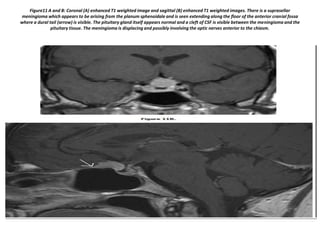

Figure11 A and B: Coronal (A) enhanced T1 weighted image and sagittal (B) enhanced T1 weighted images. There is a suprasellar

meningioma which appears to be arising from the planum sphenoidale and is seen extending along the floor of the anterior cranial fossa

where a dural tail (arrow) is visible. The pituitary gland itself appears normal and a cleft of CSF is visible between the meningioma and the

pituitary tissue. The meningioma is displacing and possibly involving the optic nerves anterior to the chiasm.